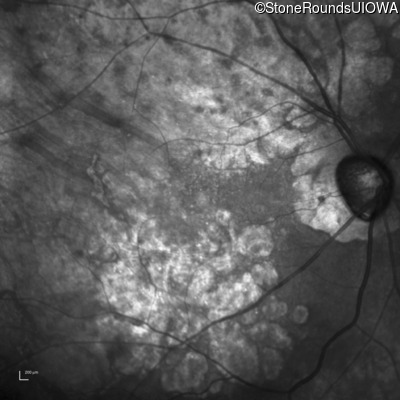

This 81 year old man began using a flashlight to read menus in his 40's. At age 75 his ophthalmologist noticed abnormal fundus findings and referred him to a retina specialist.

| Late Onset Retinal Dystrophy | C1QTNF5 | Ser163Arg AGC>AGA | AD |